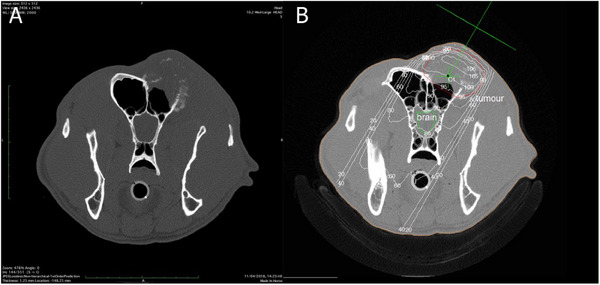

Abstract Image